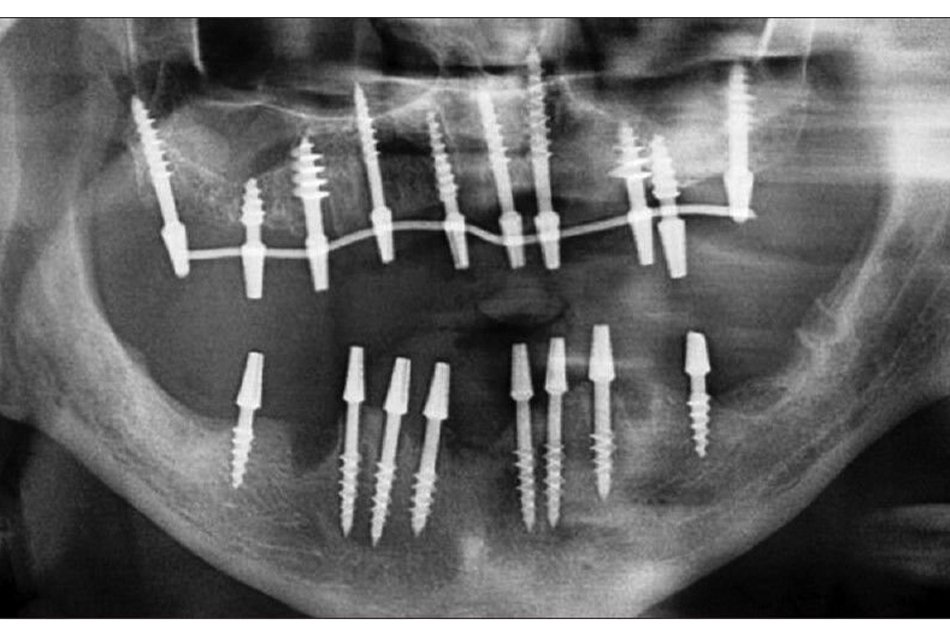

A dental implant is a small screw -shaped titanium metal that acts to restore the root portion of a missing tooth. In general, the placement of dental implants is a simple routine procedure that is usually performed with implantologist and local anesthesia. The implant will be mounted on the Jawbone in the gap left by the lost tooth. After setting up these implants, they stay until they merge with the bones around them. This is called a healing period, and after a final crown will be attached.